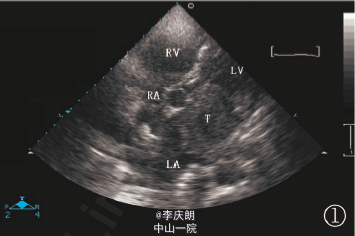

查体:皮肤青紫,二尖瓣听诊区可闻及舒张期隆隆样杂音。辅查:超声心动图示:左房内见异常实质性回声,形状不规则,回声强度中等,分布均质,内呈点状回声,附着于房间隔下部、主动脉根部上,有一定活动度,瘤体崁顿在二尖瓣口,瘤体与左上肺静脉口相连。肺部CT:双肺多发转移瘤。

诊断:甲状腺癌双肺和心脏转移。处理:在全麻下行左心房占位摘除术,术中见左上肺静脉完全被瘤体堵塞,肿瘤一直延伸入左肺,不能完整切除,术后病理证实为甲状腺癌转移癌栓(髓样癌)。